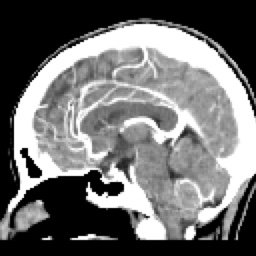

SIMPLE FINO SAG (9) 75 images

ARTERIAL FINO SAG (11) 78 images

HUESO FINO SAG (14) 75 images